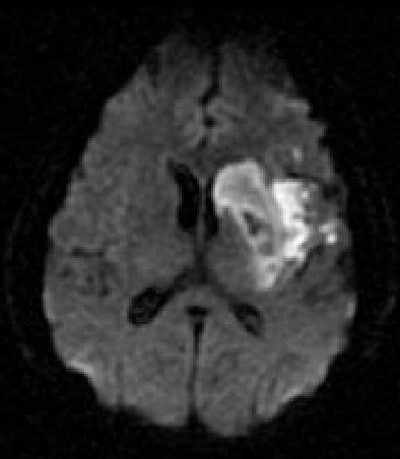

![]() |

| Diffusion-weighted image as well as fluid-attenuated recovery T2-weighted images obtained two days after the initial perfusion CT and MRI demonstrate a hyperintense area close to that on the perfusion CBF and MTT maps and the initial diffusion-weighted imaging. A slight penumbra loss is demonstrated. Images courtesy of Dr. Sotirios Bisdas. |